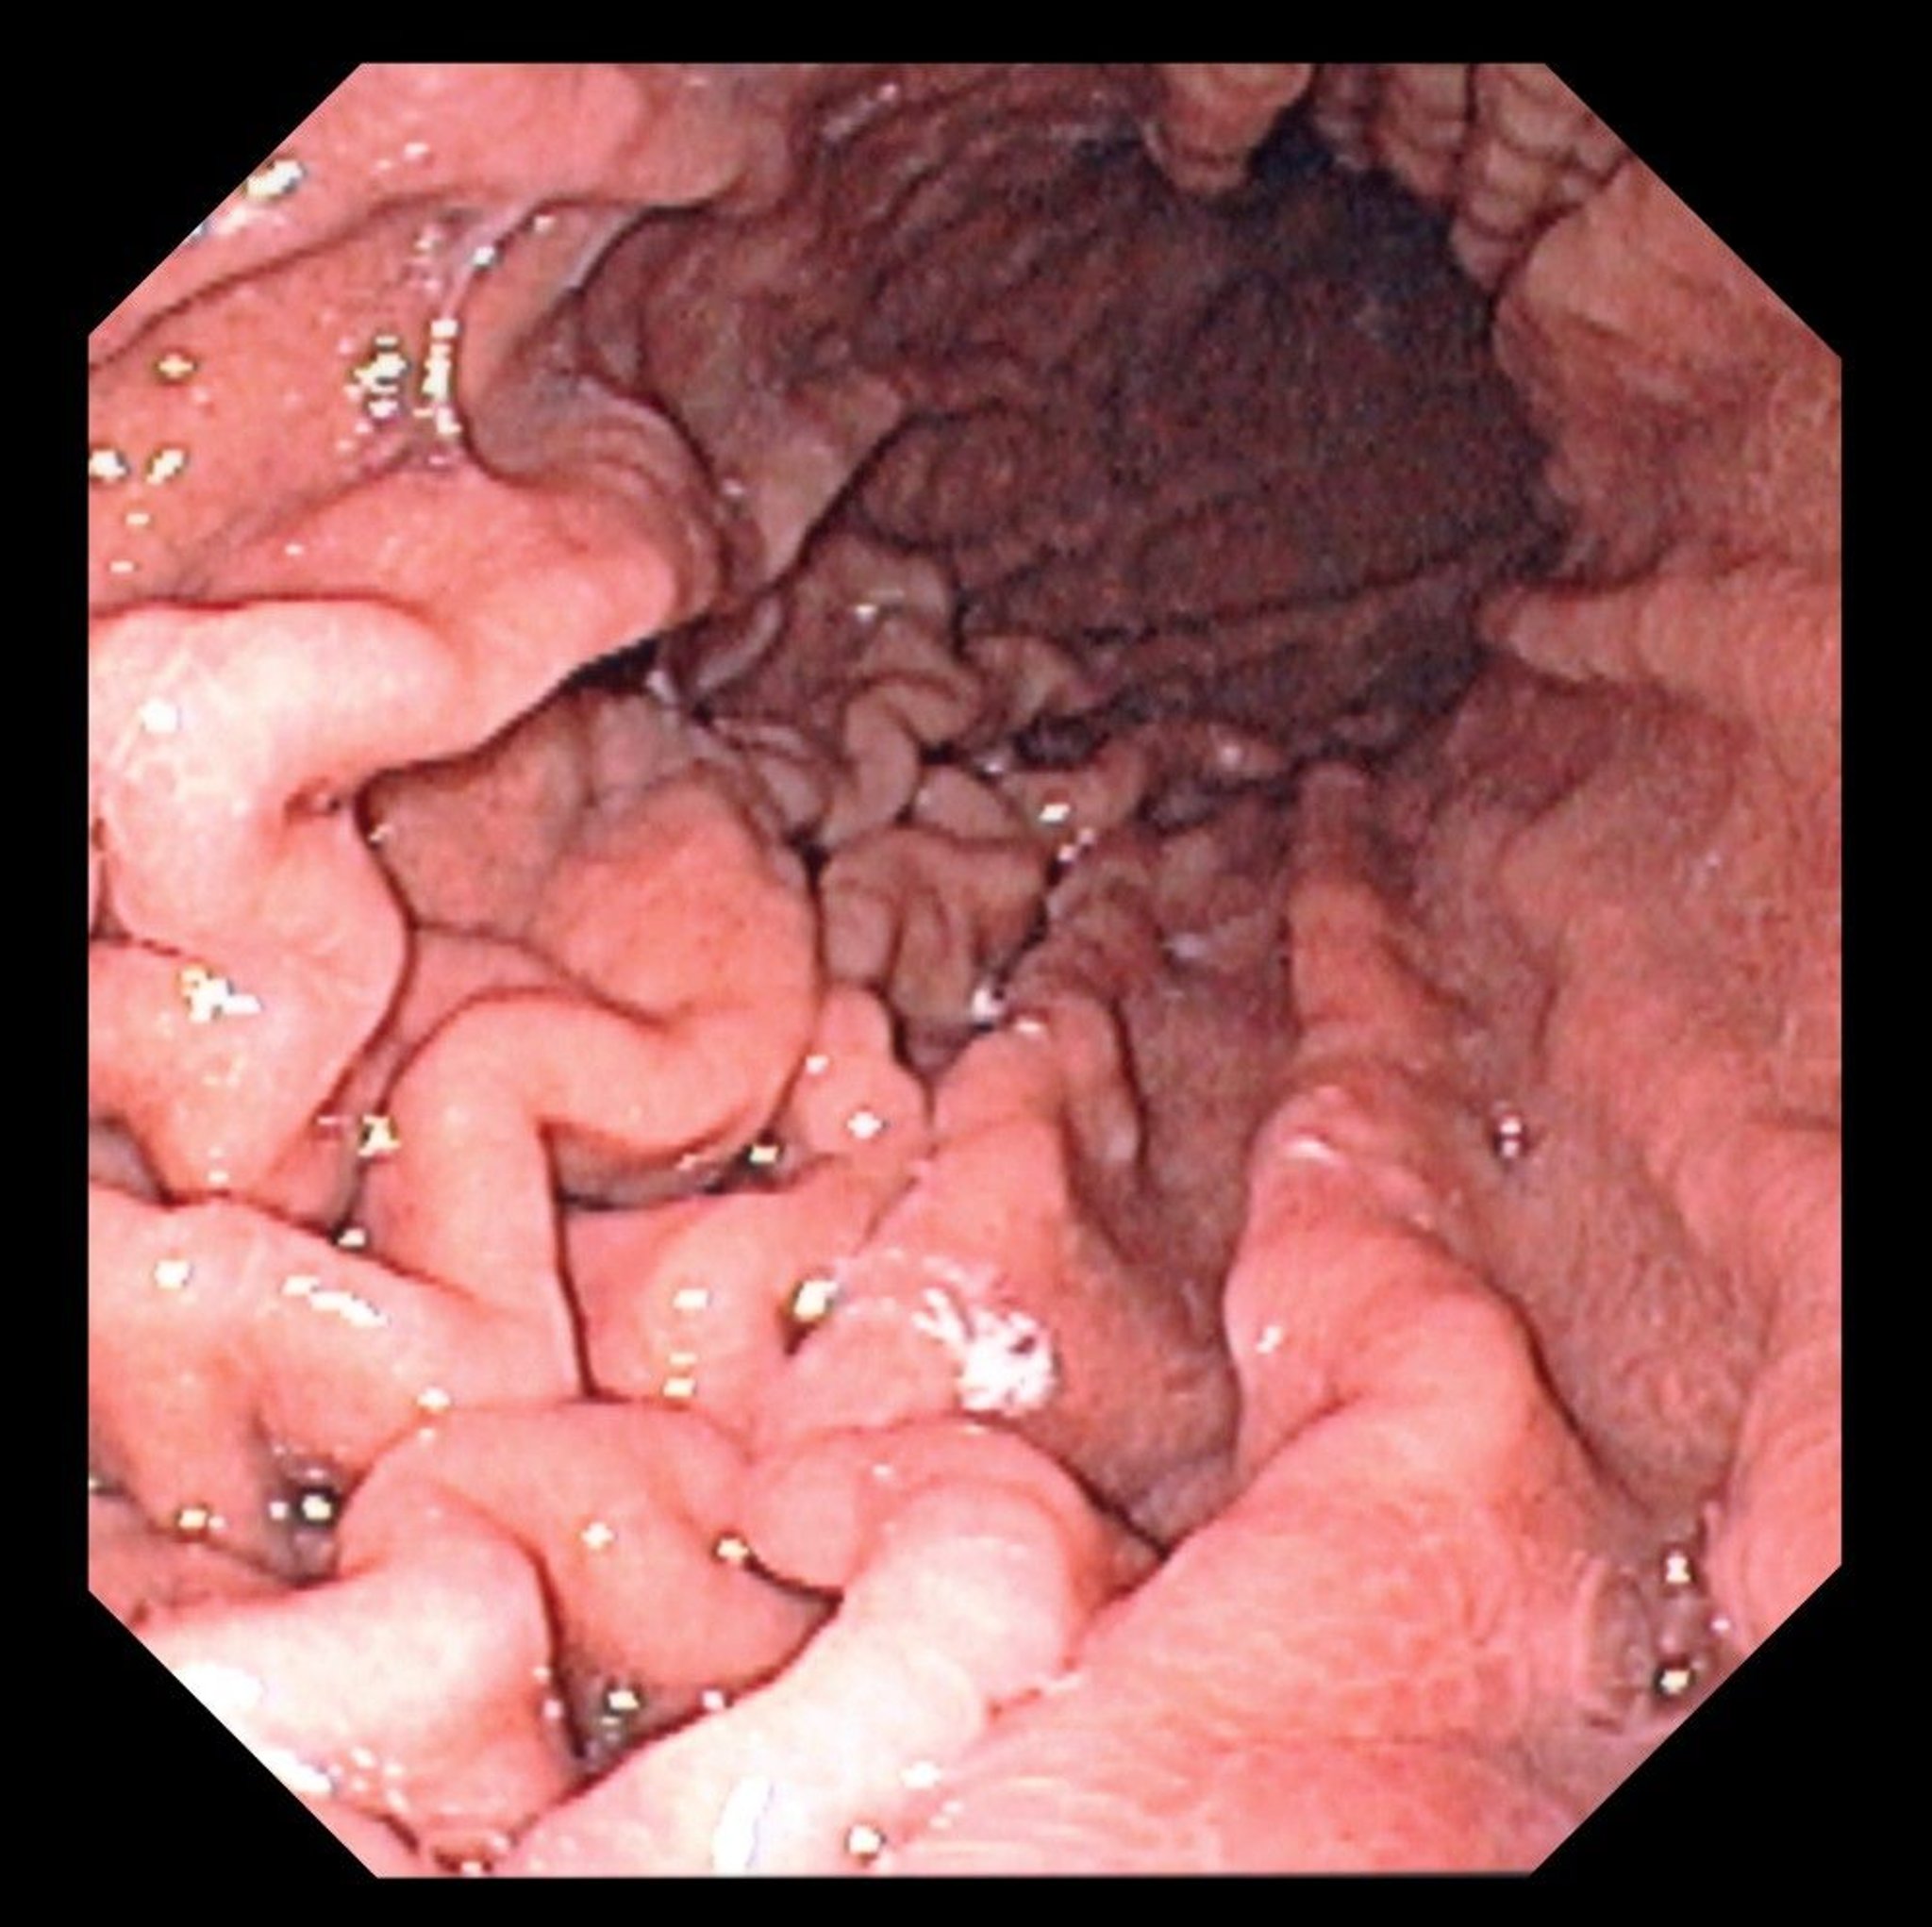

This photo shows an endoscopic view of a normal stomach fundus with characteristic gastric folds.